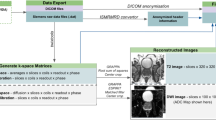

At present time, the processing and interpretation of prostate mpMRI data in clinical routine is entirely performed by human experts (radiologists) who, while competent, are time-limited, cost-intensive, and cannot be easily scaled to meet increasing imaging demands [8]. Furthermore, human performance is dependent on experience and training, leading to significant variability between observers [9,10,11]. In contrast to purely qualitative interpretation, artificial intelligence (AI) exploits the quantitative nature of mpMRI data. AI can automate and support (parts of) the radiological workflow (Fig. 1), improve diagnostic accuracy, reduce costs, and alleviate the workload of healthcare personnel.

All the datasets were confirmed to have been collected with institutional/ethical review board approval, except for I2CVB [23], Prostate158 [39], and QUBIQ21 [17], for which this information was not found. The datasets are all anonymized. Anonymization is becoming increasingly difficult in our online world in terms of data strictly not being traceable to patient information. Radiological images are almost always acquired, exchanged, and stored in DICOM format. The DICOM header is very rich in information that could lead to tracing back to the patient. The DICOM standard defines security concepts for anonymization, and public tools that implement this are available [40]. A simpler solution is to provide images in non-DICOM format, which contain header with minimal information. The drawback of non-DICOM images or very strongly anonymized DICOM images is that relevant scientific information may get lost. Public prostate MRI data should preferably be carefully anonymized DICOM images with as many tags preserved as possible. The Cancer Imaging Archive provides a very strong DICOM anonymization procedure with the most comprehensive set of DICOM tags available for scientific research [41].